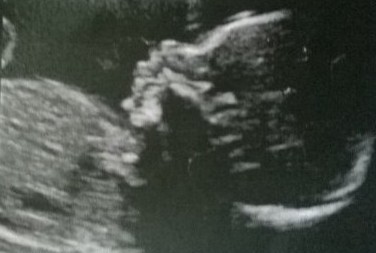

Can someone help in guessing my baby's gender by head shape?

Boy skull, but that is just for fun! Do you have any 12-14 week nub shots or any potty shots from your 20 week scan?